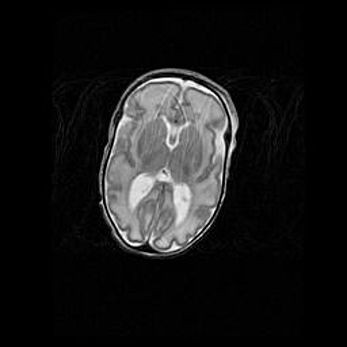

Сообщающаяся гидроцефалия. Кистозная энцефаломаляция головного мозга.

Возраст: 3 месяца 4 дня

Вес: 3100 г

Пол: женский

Окружность головы: 34 см

Срок гестации: 31 неделя

Кистозная энцефаломаляция головного мозга - одна из форм поражения головного мозга в детском возрасте. Характеризуется возникновением множественных и распространённых кист в коре, белом веществе и подкорковых образованиях головного мозга у плодов, новорождённых и детей раннего возраста. Развитие кистозной энцефаломаляции связано с внутриутробной асфиксией и гипотонией, родовой травмой, тромбозом синусов, пороками развития сосудов, инфекциями, сепсисом и другими причинами. Наиболее значимые инфекционные агенты: вирусы простого герпеса, цитомегалии, краснухи, токсоплазмы, энтеробактерии, золотистый стафилококк и другие.